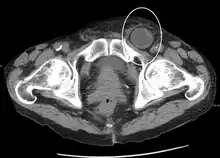

An incarcerated inguinal hernia as seen on cross sectional CT scan

When assessed by ultrasound or cross sectional imaging with CT or MRI, the major differential in diagnosing indirect inguinal hernias is differentiation from spermatic cord lipomas, as both can contain only fat and extend along the inguinal canal into the scrotum.[22]

On axial CT, lipomas originate inferior or lateral to the cord, and are located inside the cremaster muscle, while inguinal hernias lie anteromedial to the cord and are not intramuscular. Large lipomas may appear nearly indistinguishable as the fat engulfs anatomic boundaries, but they do not change position with coughing or straining.[22]